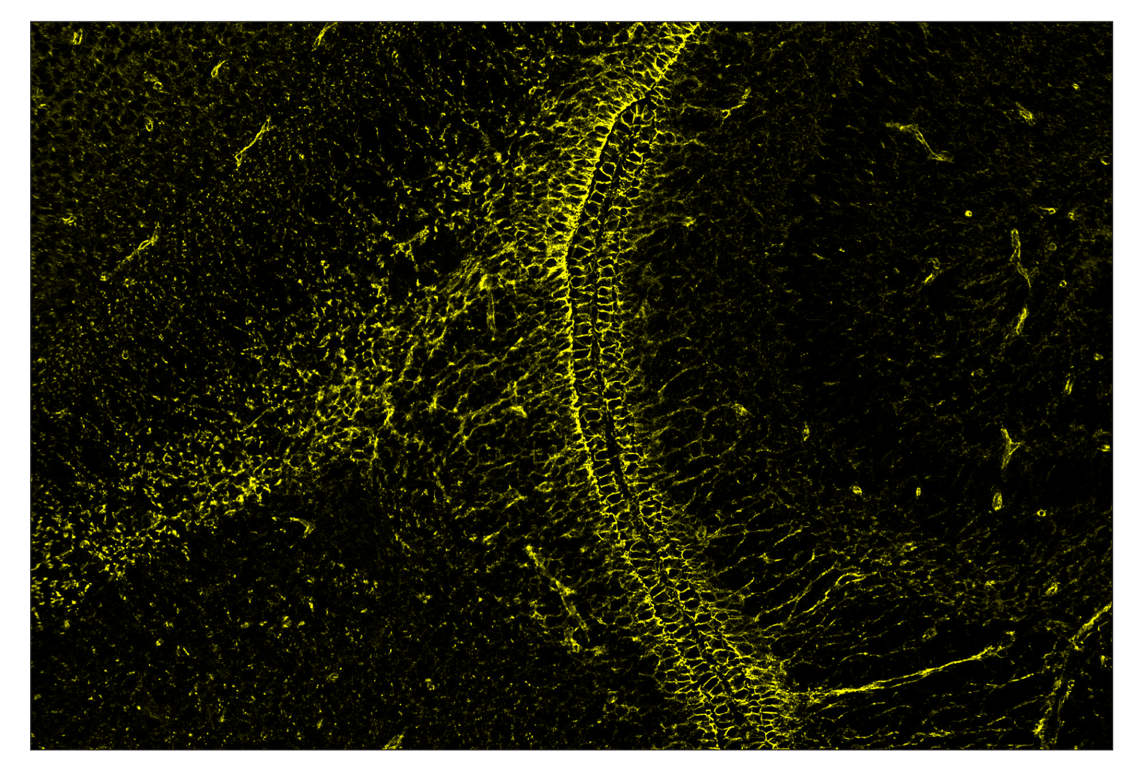

SignalStar™ multiplex immunohistochemical analysis of paraffin-embedded mouse brain using β-Catenin (D10A8) & CO-0108-594 SignalStar™ Oligo-Antibody Pair #83149 (yellow). All fluorophores have been assigned a pseudocolor, as indicated. Staining was performed on the BOND RX autostainer by Leica Biosystems.

Immunohistochemistry Image 2: beta-Catenin (D10A8) & CO-0108-750 SignalStar<sup>™</sup> Oligo-Antibody Pair